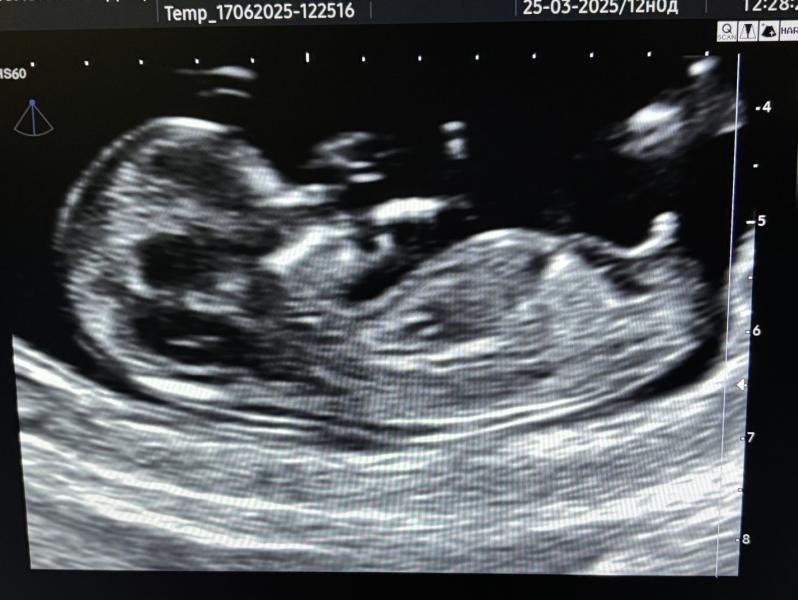

Всем привет, сегодня ходила на 1 скрининг. Врач спросила говорить ли пол. И сказала, что мальчик.

И мне кажется, на фото прям понятно, что пацан 😹

По лицу девочка. То, что внизу, возможно, пуповина для полового бугорка как будто высоковато

По половому бугорку мальчик 99%